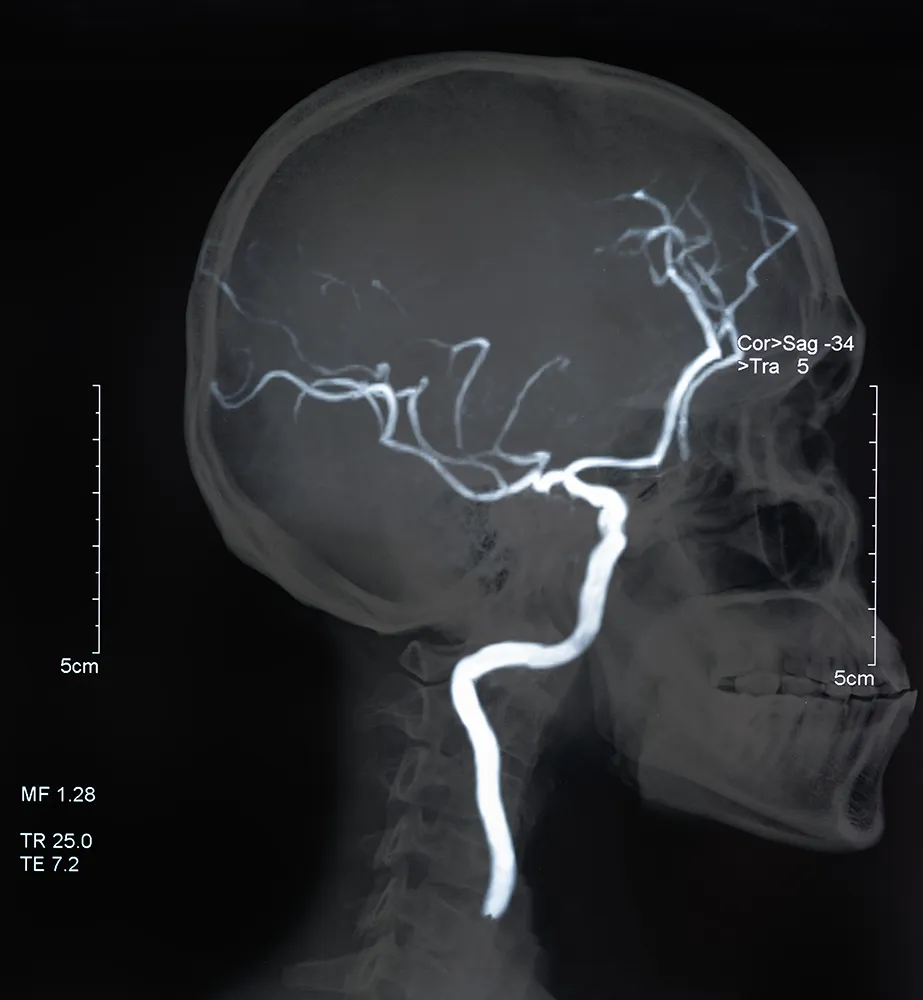

뇌경색은 크게 보면 뇌졸중의 증상으로 뇌혈관이 막히는 현상을 말합니다. 뇌경색은 동맥경화로 혈관이 좁아지는 상태로 결국에는 혈관이 막혀 뇌경색과 혈액 덩어리가 막히는 뇌혈전 두 가지로 나눌 수 있습니다.

뇌경색은 뇌의 동맥이 막혀 혈액순환이 원활하지 않아 발생하는 질병으로 큰 문제로는 어느 날 갑자기 찾아온다는 것입니다. 그렇기 때문에 아래와 같은 전조 증상이 있었다면 간과하지 말고 즉시 병원에 방문하여 증상을 이야기하고 진료를 받아보아야 합니다.